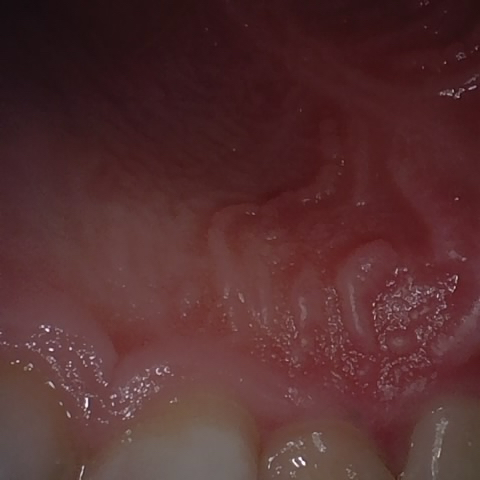

Annotated as "Good"